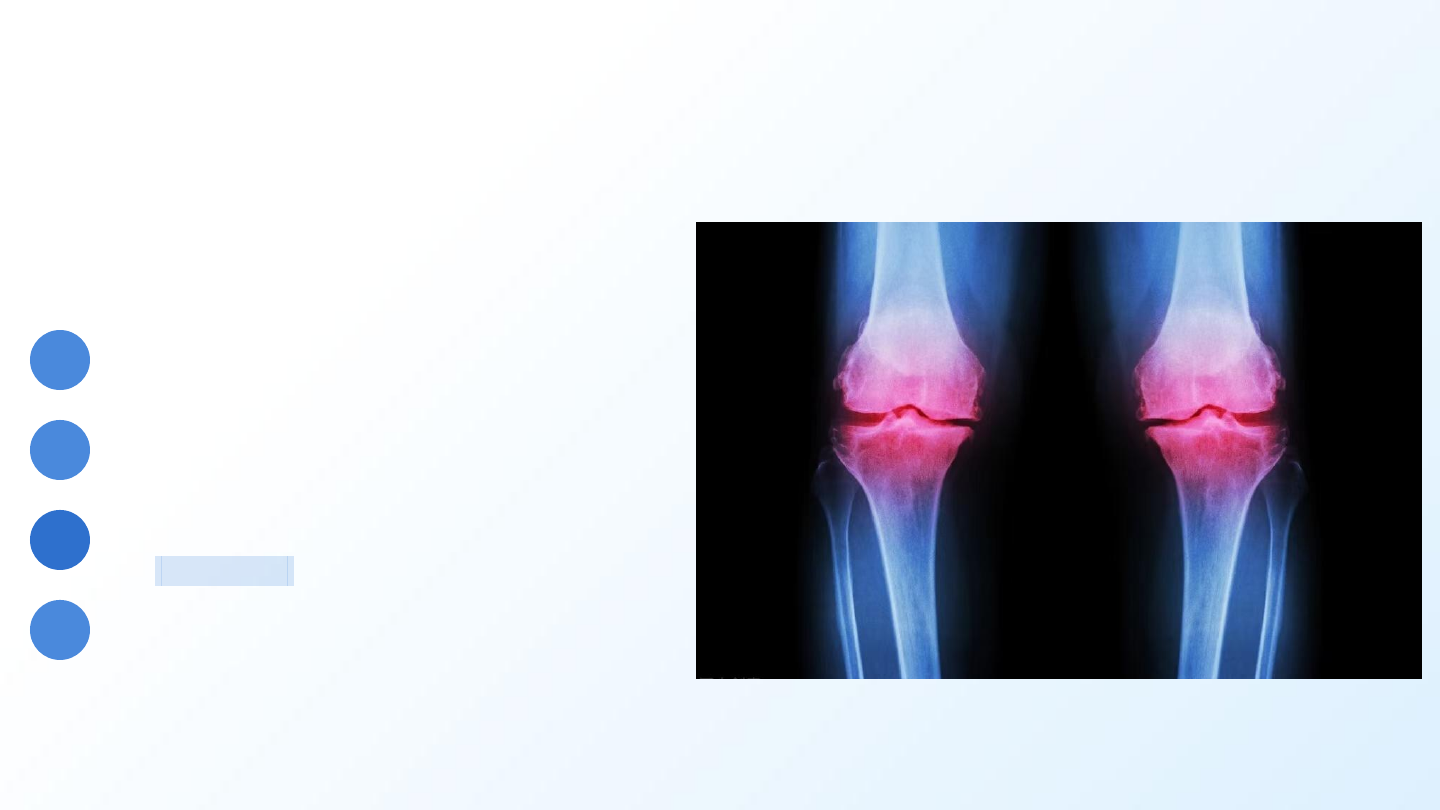

退行性病变

软骨磨损才是核心

骨性关节炎并非简单的“骨刺病”,其本质是关节软骨的磨损

与丢失,是身体的“轴承”出了问题。

核心病变: 关节软骨退变、磨损、丢失。

继发改变: 机体为维稳,代偿性长出骨赘(骨刺)。